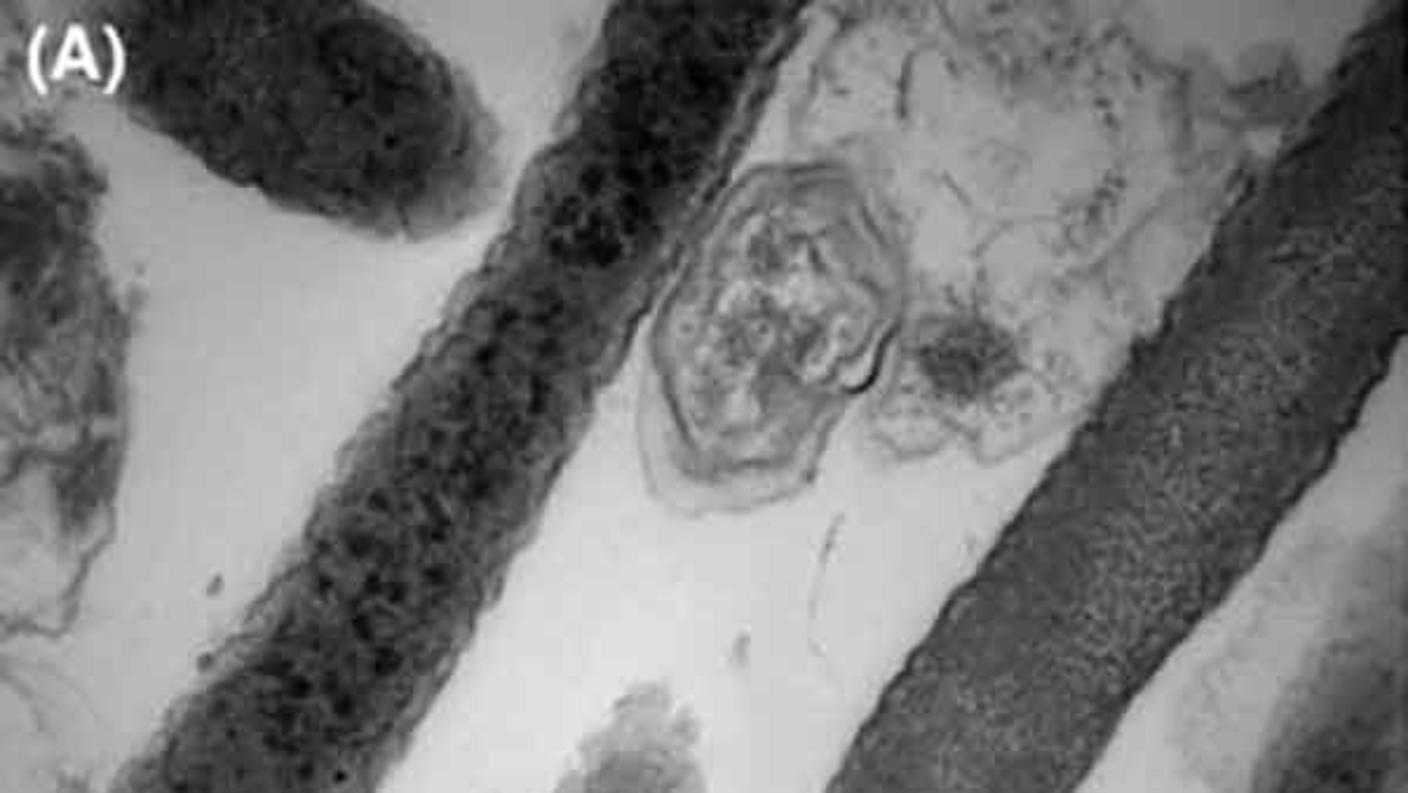

Those differences included Fna C2’s higher resistance to acid, which could allow it to potentially reach the intestines directly from the mouth, through the stomach. Fna C2 also had the ability to hide inside certain tumor cells, which could protect it from the immune system. And it was able to use nutrients found in the gastrointestinal tract, which are very different from those found in the mouth.